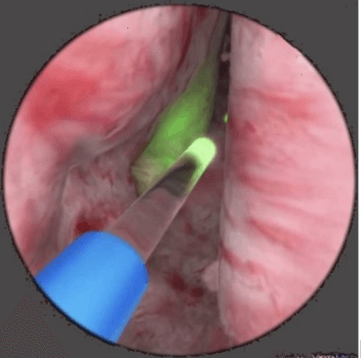

Bir anlamda; cerrahların çıkardıkları dokunun miktarından haz bulma ihtiyaçları diğer tarafta hastaların beklentileri zaman içerisinde Holmiyum Lazer (HoLEP) yönteminin geliştirilmesiyle sonlandı (Resim 3). Hekimin fotoğraflarla dökümante ederek hastaya ve yakınlarına gösterdiği prostat dokusuyla dolu kapların gurur verici etkisi karşılığında göreceli uzun ameliyat süresi, cinsel yaşama %80 düzeyinden fazla olumsuz yan etki yöntemin yüksek başarı oranına leke düşürdü.

Resim 3. HoLEP yöntemiyle iyi huylu prostat büyümesi ameliyatı.